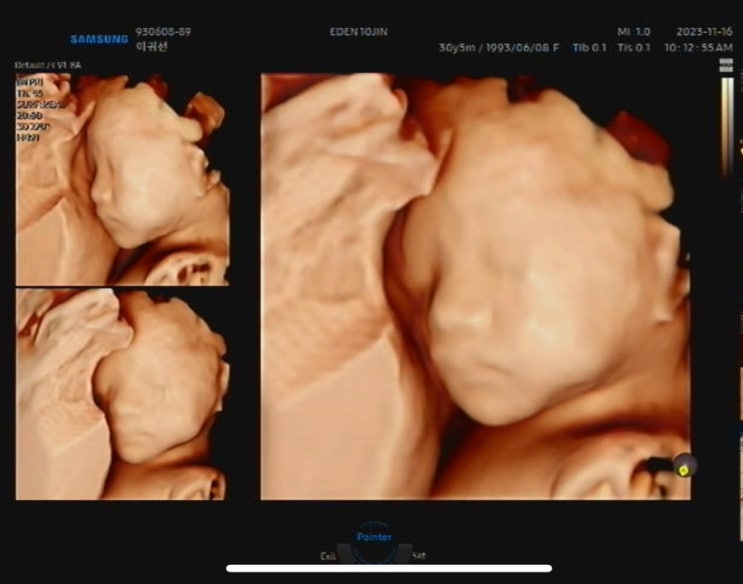

제가 임신한지도 벌써 30주가 넘었어요 초기때는 시간이 정말 안갔는데.. 후기되니까 이렇게 훅훅 가버린다...